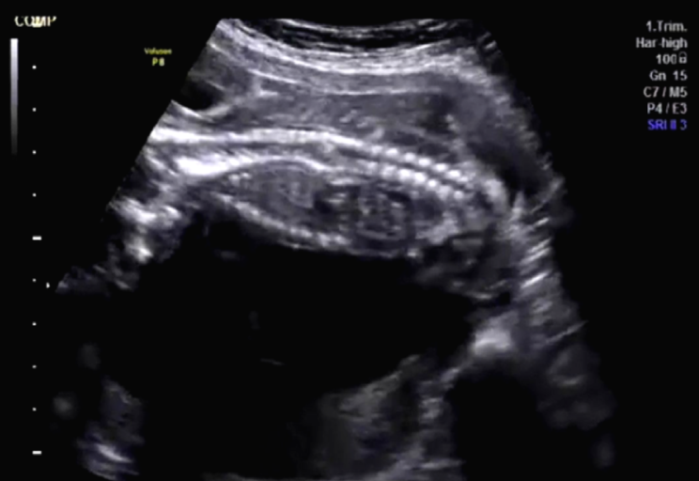

Figure 1. First view of coronal section of the fetal spine. (Image courtesy of Firoz Bhuvar, MD)

Imaging studies: This routine transabdominal obstetric sonography was performed to exclude any congenital fetal anomalies. The patient had not undergone any sonographic study prior to this scan. The images seen in Figure 1, Figure 2, and Figure 3 show the coronal section of the fetal spine and were taken during this routine sonographic examination.

In Figures 1, 2, and 3, the volume of amniotic fluid appears normal. The fetal abdomen also shows no significant abnormality. The placenta is fundic and posterior. No retroplacental hematoma is seen.

The most prominent anatomy in these images is the fetal spine. The fetal head is to the left of the images, and the fetal lower limbs are to the right of the images. The upper cervical and thoracic spines appear normal. However, there is an abnormality within the lower thoracic vertebrae that appears as an echogenic lesion within the spinal canal. It looks linear and extends within the mid-portion of the spinal canal. We cannot further distinguish the abnormality in this region. What are the diagnostic possibilities based on these images, at this stage?

Shall we call this some form of spinal dysraphism or neural closure defect? The most common anomalies that arise are tethered spinal cord, thickened filum terminale, neurenteric cyst, meningocele, and dermal sinus tract. Also, there are the remote possibilities of diplomyelia and diastematomyelia. Let us examine each of these possibilities.